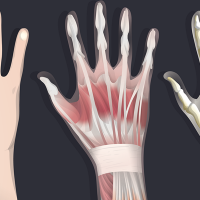

Know Your Anatomy